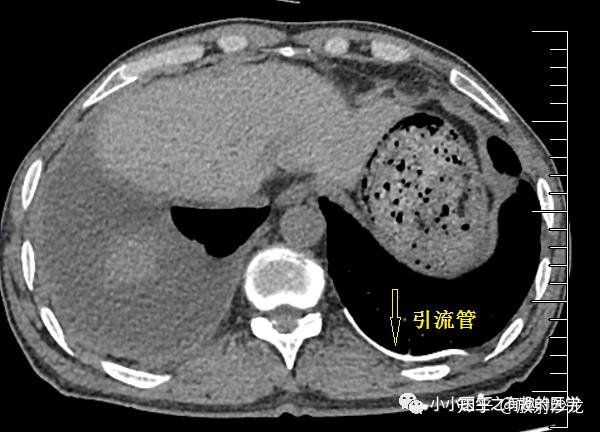

游离性胸腔积液